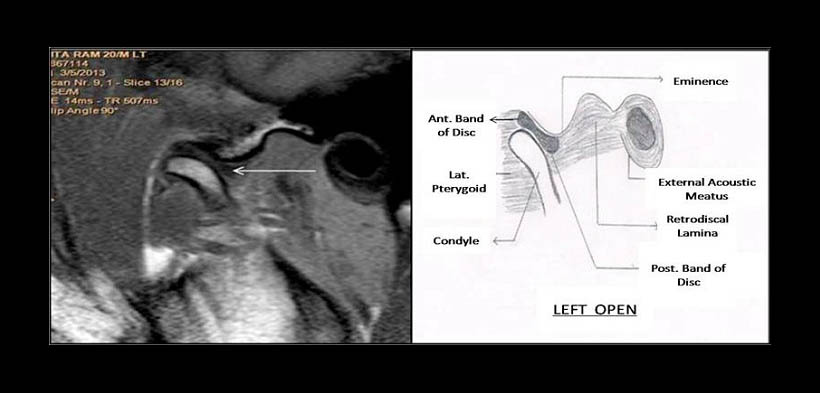

Fig. 2. POSICIÓN NORMAL DEL COMPLEJO CÓNDILO DISCO EN BOCA ABIERTA. Resonancia magnética de un paciente en boca abierta. Se muestra una adecuada posición y relación del disco articular con respecto al cóndilo mandibular y la eminencia articular del hueso temporal.

Fig. 4. DESPLAZAMIENTO DISCAL ANTERIOR CON REDUCCIÓN EN BOCA ABIERTA. Resonancia magnética de un paciente en boca abierta. Se muestra la reducción del disco a una adecuada posición y relación del disco articular con respecto al cóndilo mandibular y la eminencia articular del hueso temporal.